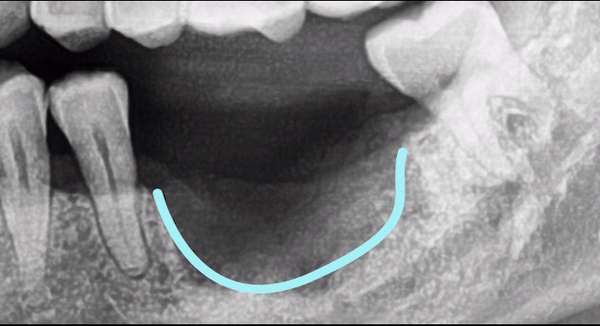

하악 매복 사랑니 발치 Before & After

상 · 하악 매복 사랑니 발 Before & After